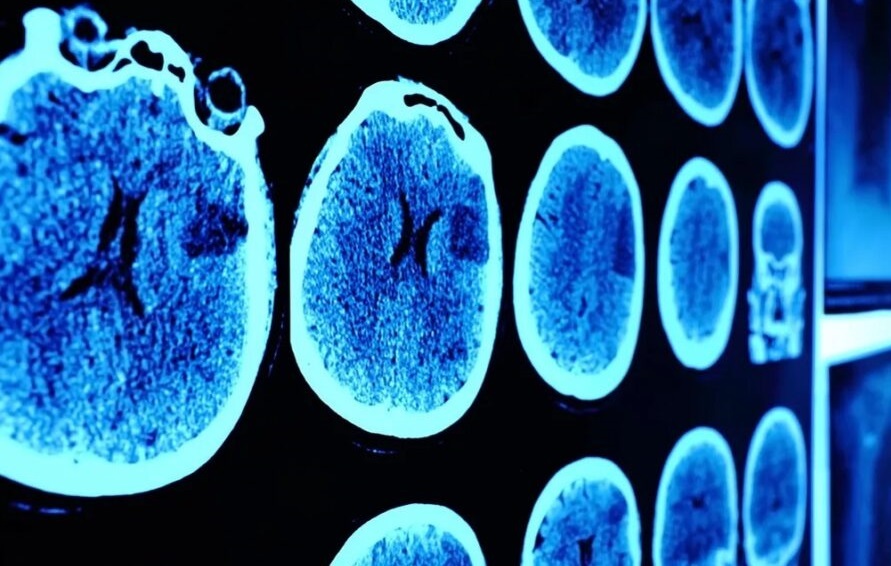

DIPG یک تومور تهاجمی و بدخیم مغزی است که در بخشی از ساقه مغز به نام پونز ایجاد می شود. تومور DIPG را نمی توان با جراحی برداشت و معمولاً با رادیوتراپی درمان می شود – که گاهی اوقات فقط پیشرفت بیماری را کند می کند.

در آن زمان خانواده لوکاس برای معالجه به فرانسه آمدند تا پسر نوجوان را در برنامه درمانی آزمایشی BIOMEDE ثبت نام کنند. در این برنامه از داروهای آزمایشی مختلفی برای DIPG استفاده می شود و لوکاس از همان ابتدا به خوبی به داروی Everolimus پاسخ داد و مدتی بعد اثری از تومور در اسکن مغز مشاهده نشد. دکتر گریل می گوید که با کمک این دارو بین ۱۰ تا ۱۵ سال طول می کشد تا این تومور از بین برود و لوکاس زودتر از این زمان تحت درمان قرار گرفت. از سوی دیگر، سایر کودکانی که این دارو را مصرف می کردند، نتایج امیدوارکننده ای نشان دادند، اما مانند لوکاس، تومورهای آنها به طور کامل ناپدید نشد.